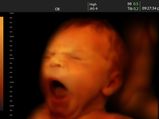

குழந்தைகள் கருவறையில் அழுக காரணம் என்ன? இப்படி அழுவது நல்லதா?